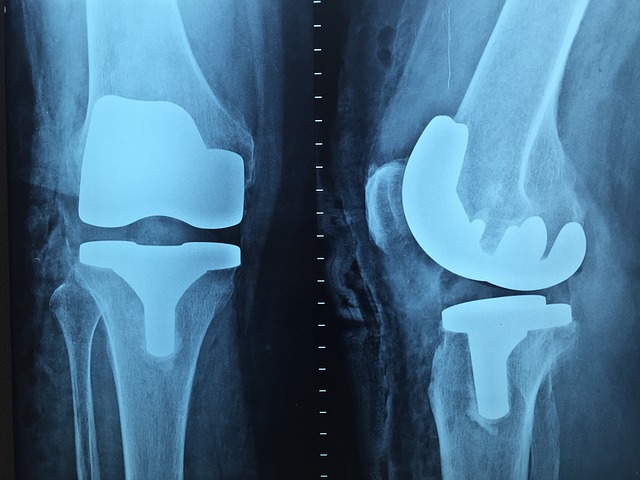

- X-ray 검사 – 연골이 마모되었거나 뼈가 자란 증상(골극, Bone Spur) 확인 가능.

- MRI 검사 – X-ray로 보이지 않는 연골과 연조직 손상을 더 정밀하게 검사.

- 인공관절 치환술 – 심한 관절염의 경우 손상된 관절을 인공관절로 교체.